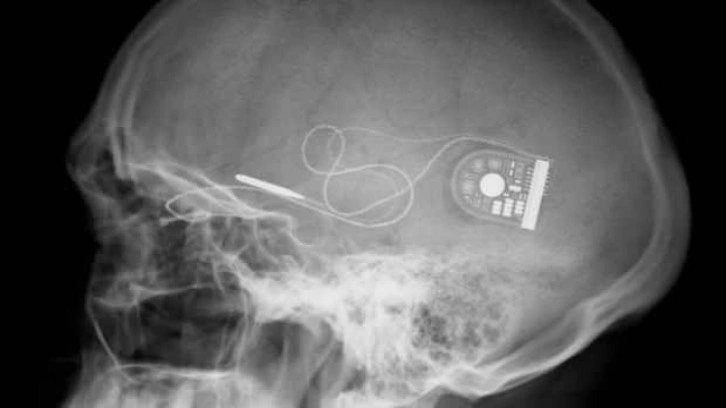

The Defense Advanced Research Projects Agency (DARPA), ABD ordusu için ileri teknoloji ürünler üretmekten sorumlu ABD Savunma Bakanlığı’na bağlı bir devlet kurumu. DARPA'ya son olarak ABD Savunma Bakanlığı tarafından bir askerin beynine yerleştirilecek ve anılarını kaydedecek implant geliştirme emri verildi. İmplant askerin beyninde adeta kara kutu olarak görev alacak. Asker bu implant ile hafıza kaybına uğrasa dahi implant bu anıları geri yükleyebilecek.

DARPA, konuyla ilgili olarak Medtronic gibi beyin implantları konusunda uzman ticari şirketlerden teklif bekliyor. Parkinson hastalığının etkilerini azaltmak için beyin implantları geliştiren Medtronic şirketi DARPA'nın bu teklifine sıcak bakıyor. Ayrıca IBM gibi büyük Ar-Ge bütçeleri olan şirketler de bu projeye katılmayı hedeliyor.